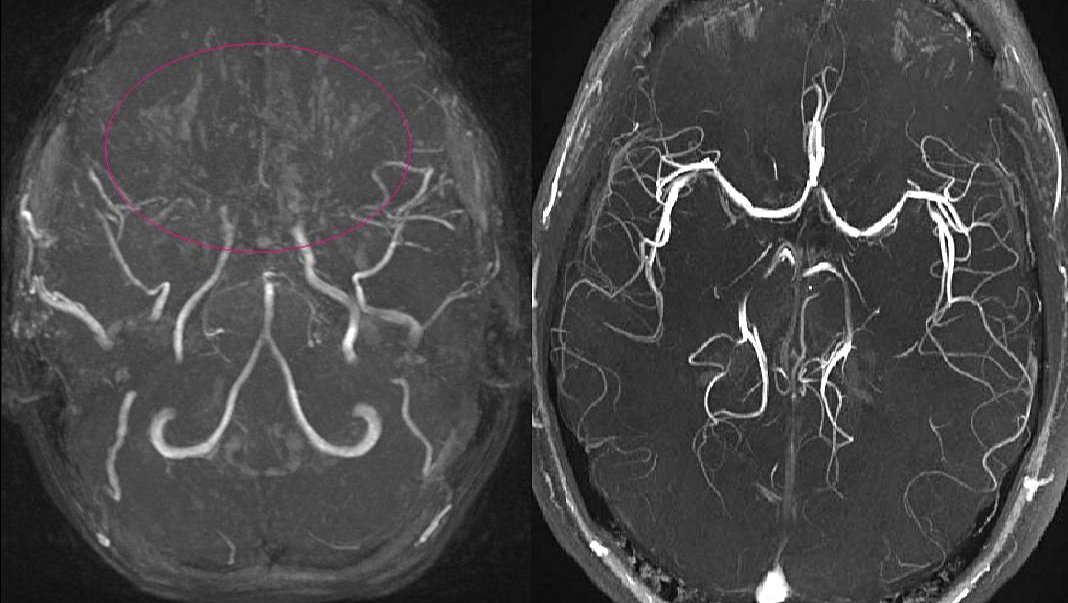

Moyamoya hastalığı; beyinde bulunan bazı arterlerin (damarların) daralması sonucunda ortaya çıkan kronik, ilerleyici bir serebrovasküler hastalıktır. Bu hastalık, Willis poligonunu oluşturan arterlerin bilateral, ilerleyici darlığı veya tıkanıklığına bağlı olarak gelişen kollateral damarların karakteristik bir özelliği olarak tanımlanır. Bu durum, beyne yeterli kan akışının sağlanamamasına ve oksijenin yetersiz olduğu bölgelerde iskemik semptomlara (kan eksikliğinden kaynaklanan belirtiler) yol açabilir. Hastalığın sebepleri net olarak bilinmemekle birlikte, genetik ve konjenital faktörlerin etkili olduğu düşünülmektedir. Ayrıca, bazı tümöral hastalıklarla birlikte görülebilir.[1], [2], [3], [4]

Moyamoya hastalığının teşhisi, nadir görülmesi ve bariz olmayan belirti ve semptomlardan dolayı zor olabilir. Teşhis, klinik bulgular ve görüntüleme bulguları temelinde şüphelenilerek konur. Teşhisin doğrulanması için standart yöntem serebral anjiyografi olarak kabul edilir.[7]

Serebral anjiyografi, moyamoya hastalığını doğrulamak için kullanılan standart bir yöntemdir. İşlem sırasında, kontrast madde enjeksiyonu ile beyin damarlarının röntgen filmi çekilir. Ancak, bu yöntem intravenöz kontrast kullanımına bağlı alerjik reaksiyonlar ve nadiren kontrast maddeye bağlı böbrek hasarı gibi riskleri içerebilir.[7]

Tanıda etkili olan bir diğer unsur, hastanın klinik belirtileri ve görüntüleme bulgularıdır. Moyamoya hastalığının belirgin bulguları genellikle supraclinoid iç karotis arterleri ve bunların proksimal dallarını içerir.[7]